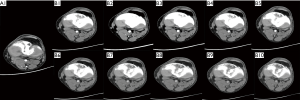

The mean attenuation was higher in group B2 and was lower in group B3 compared with group A1, but neither difference reached statistical significance. Furthermore, the mean attenuation in group B1 and groups B4–B10 was lower than that in group A1 (P<0.05). The mean noise was similar in group B2 (P>0.05) to that in group A1, but lower in group B1 and groups B3–B10 (P<0.05). The mean SNR and CNR in group B2, as well as the mean SNR in group B3, were higher than those in group A1 (P<0.05), and the mean CNR in group B3 was similar to that in group A1 (P>0.05). The mean SNR and CNR in group B1 and groups B4–B10 were similar or significantly lower than those in group A1 (Figure 1 and Table 2). Example axial images of group A1 and groups B1–B10 are shown in Figure 2.

Subjective IQ scores in groups B2 and B3 were similar and showed a declining trend in group B4 compared with those of group A1 (Table 3). The differences between B2 versus A1, B3 versus A1, and B4 versus A1 were not significant. Scores of group B1 and groups B5–B10 were significantly inferior to those of group A1 (P<0.05). Example images are presented in Figure 3. Interobserver agreement was good to excellent (range, ĸ≥0.688; P<0.05).